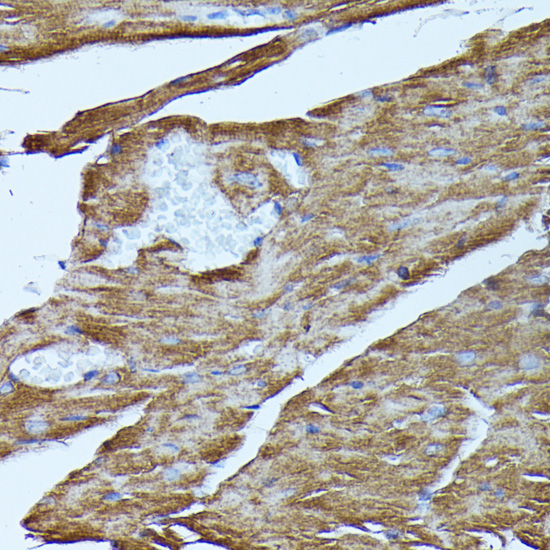

Immunohistochemistry of paraffin-embedded mouse heart using FGD1 antibody.